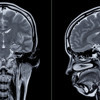

17 ila 95 yaş arasındaki 4726 kişinin 12 binden fazla beyin taramasını inceleyen araştırmacılar, kadınlar ve erkekler arasında "küçük ama sistematik farklılıklar" tespit etti.

Araştırmacılar katılımcıların her birini en az iki kez MR taramasından geçirdi. Ortalama üç yıl aralıklı yapılan bu taramalarda yaşlanmaya bağlı değişimler gözlemlenebildi.

Bu şekilde beyin hacmi, yüzey alanı, korteks kalınlığı, gri ve beyaz madde oranı gibi pek çok değişken incelendi. Böylece şimdiye kadar bu konuda yapılan en büyük araştırmalardan birine imza atıldı.